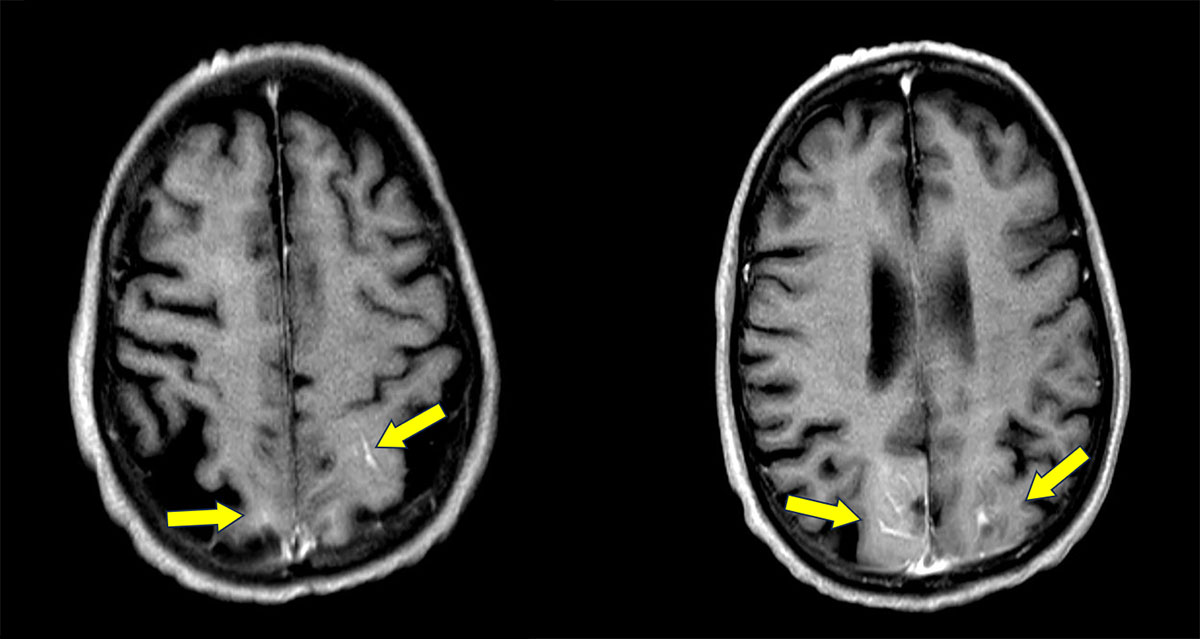

Day 1

T2 FLAIR

POST CONTRAST T1 FLAIR

MRI Brain (Day 1):

- FLAIR hyperintensities in the bilateral parietooccipital region.

- Post contrast T1 FLAIR images showing leptomeningeal enhancement in the same areas.

MRI Brain (Follow Up):

Resolution of previously seen FLAIR hyperintensities and leptomeningeal enhancement in bilateral parietooccipital region.